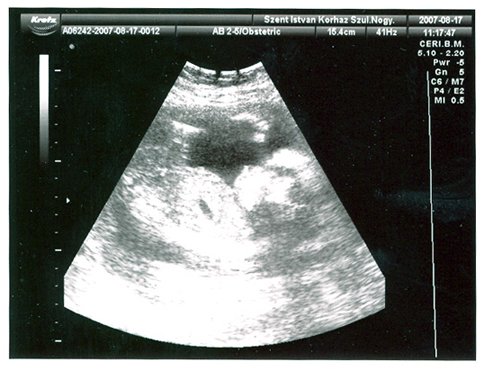

Lányok, mindenkinek köszönjük a dícséretet....egyébként úgy látjuk, hogy tiszta apuka